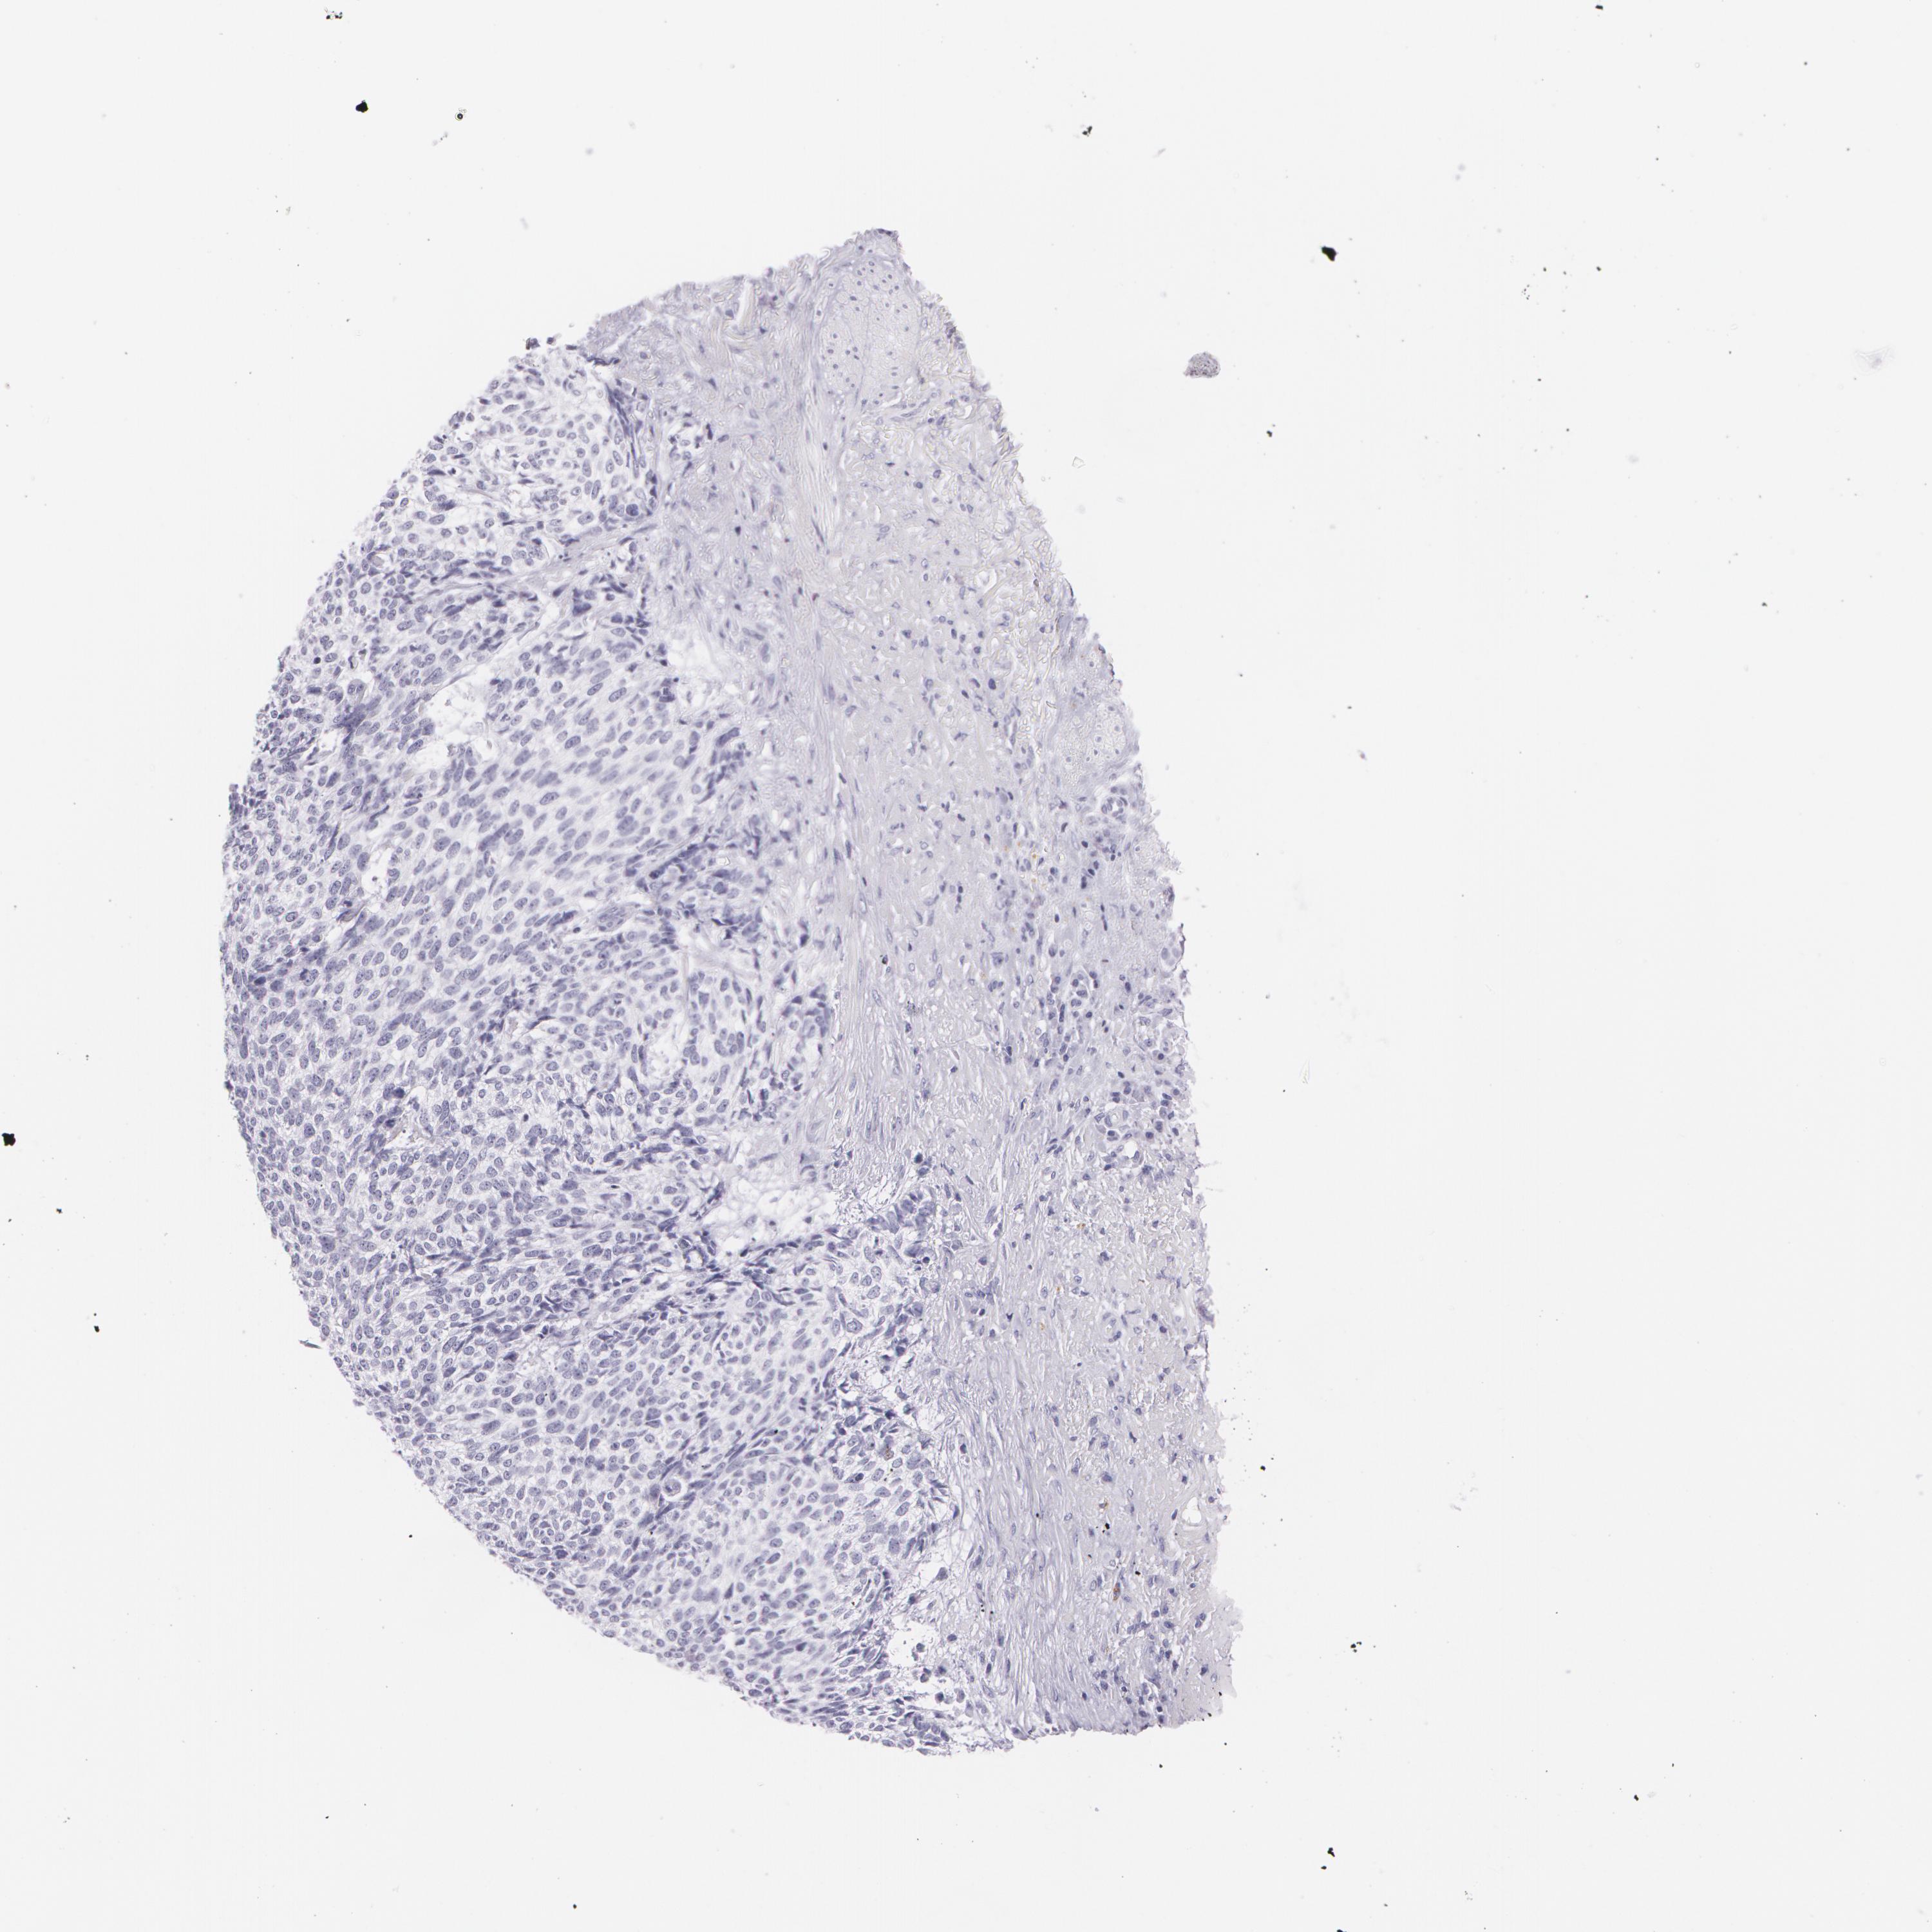

SKIN CANCER - Protein expressioni

A mouse-over function shows sample information and annotation data. Click on an image to view it in a full screen mode. Samples can be filtered based on level of antibody staining by selecting one or several of the following categories: high, medium, low and not detected. The assay and annotation is described here.

Each image is clickable and will lead to virtual microscopy that enables deeper exploration of all samples and also displays staining intensity scores, fraction scores and subcellular localization as well as patient and tissue information for each sample.

Antibody HPA014404

Squamous cell carcinoma, NOS